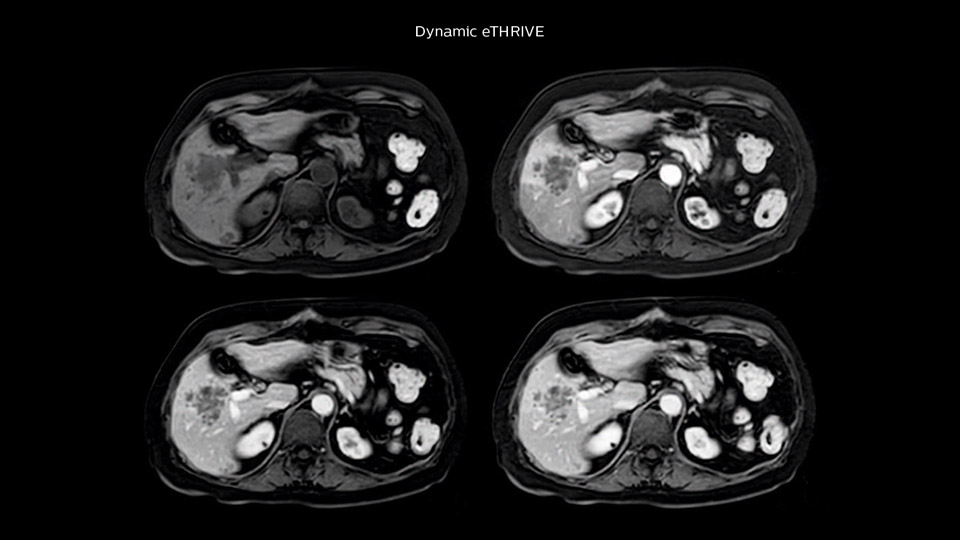

“Our liver exams are quite fast,” says Dr. Baumann. “If the patient tolerates it, we use an arms-up position to reduce the FOV and speed up the exam with dS SENSE.” “We acquire one transversal high resolution T2-weighted sequence with 3 mm slice thickness, for example for pancreas or liver lesions. Then we also add a T2 fat suppressed MultiVane XD SPIR sequence. We perform these two routinely in our liver imaging. We use high dS SENSE factors to significantly shorten scan times to 2-4 minutes, which can improve our protocol; it’s a very robust scan.” “We include mDIXON for the dynamic sequences because of the robust and homogeneous fat suppression we get with that. We had been using eTHRIVE, but we are now quite happy with mDIXON. Sometimes we use a medication to calm the bowels, to further improve the image quality.”